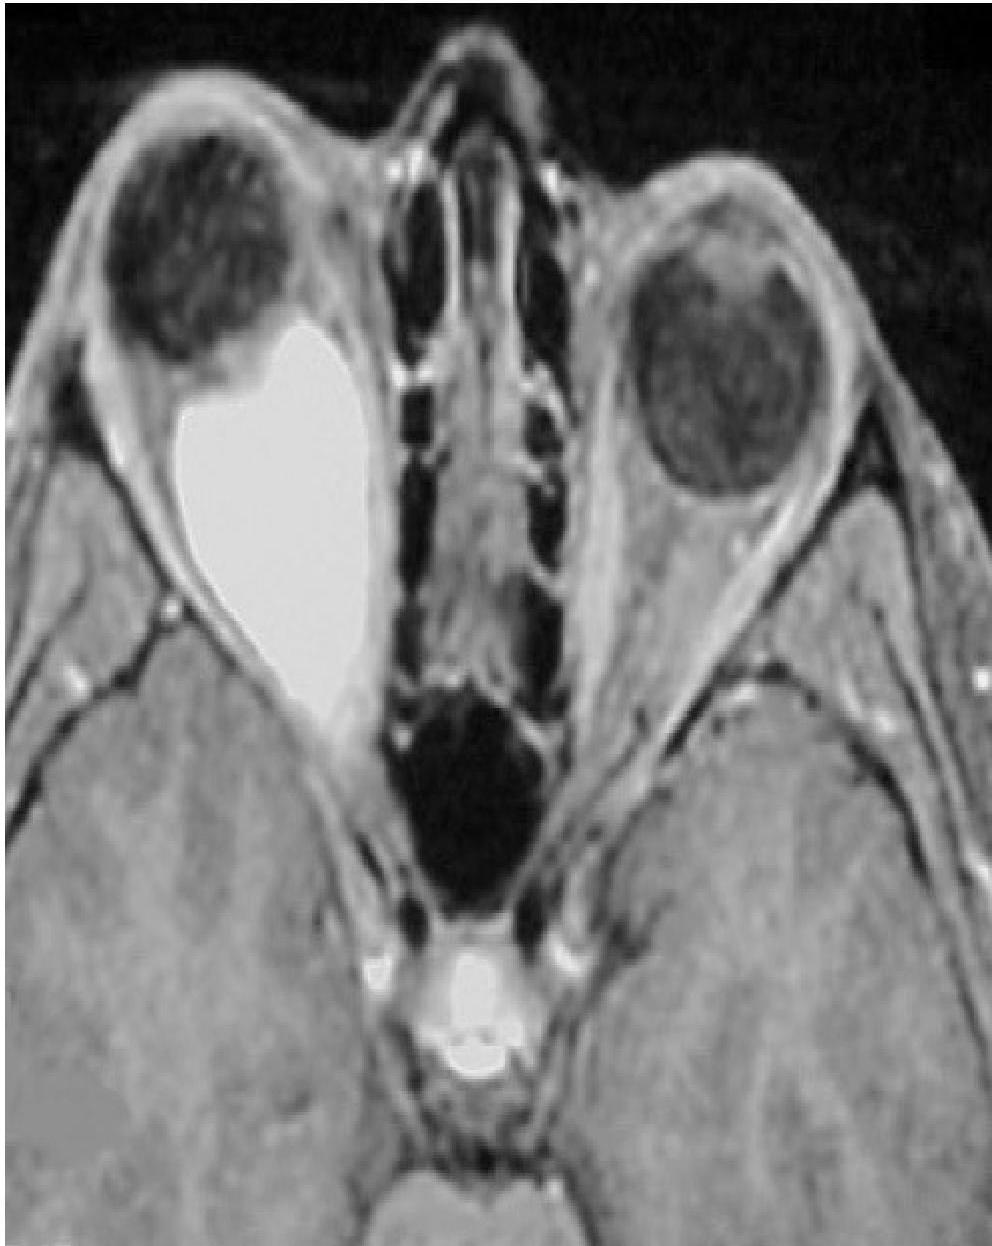

- MRI findings.

1. Bilateral Vestibular Schwannomas (Acoustic Neuromas)

- Most common tumor: Schwannomas.

- Most common affected cranial nerve: CN VIII (Vestibulocochlear nerve).